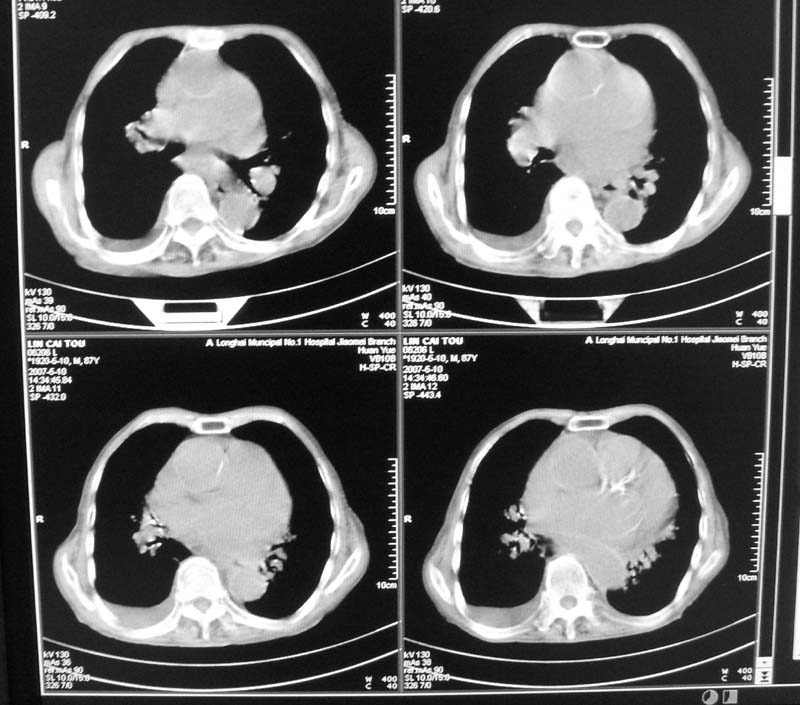

以下是引用小初学者在2007-5-12 16:26:00的发言:[br]1、心衰肺水肿两侧胸腔积液2、心包积液3、心瓣膜钙化